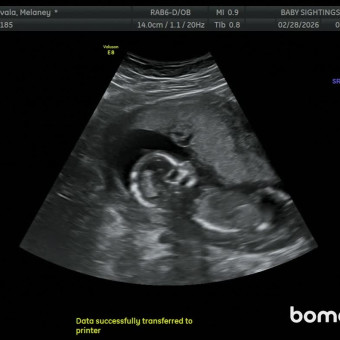

Melaney & Manuel Zavala

August 20, 2026